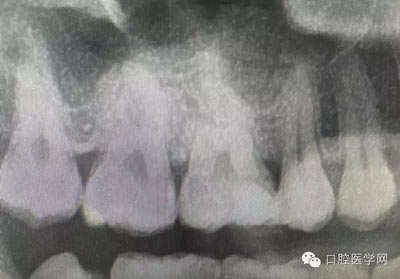

根管再治療是我們比較頭疼的,尤其是那些冠修復過的,我們有很多的麻煩需要去溝通,比如可能導致的側穿、可能沒有看到的腐質、可能導致的崩瓷,或者是后期可能出現(xiàn)冠折......這些需要我們和患者好好的溝通。全瓷冠還好些,金屬冠根測的時候很是麻煩,總之我們做修復的時候不要單純的追求速度,追求效益,適當?shù)淖⒁庀挛覀兊幕A治療和設計。

深齲或者是齲壞備洞的時候意外穿髓,我們怎么處理好些?后期出現(xiàn)的牙髓的癥狀,是我們操作的問題?比如細菌層的存在,我們沒有清理干凈?還是我們窩洞沒有進行消毒,或者是隔濕沒有做好導致的粘結出現(xiàn)問題,還是材料充填的時手法不對,導致的材料收縮過大,還是我們的光照設備出現(xiàn)了老化沒有完全達到想要的固化,還是懸空的釉質沒有去除導致的微滲漏的發(fā)生,或者是材料本身對牙髓產生的刺激,還是材料選擇的問題,或者是我們對材料的性能和說明沒有足夠的了解導致的,沒有按照材料的要求去做,還是我們自身對牙齒情況的判斷出現(xiàn)的問題......